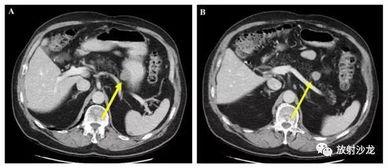

影像学检查:比如CT、MRI等,可以清晰地看到肿瘤的位置和大小。